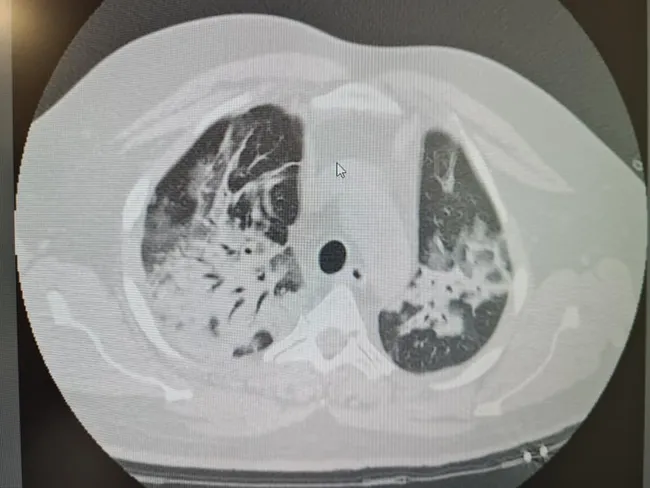

FOTO Cum arată plămânii unui tânăr cu COVID, în stare gravă la spital, după tratament cu ivermectină

Dr. Elena Copaciu, medic primar ATI, a publicat, pe pagina sa de Facebook, imagini cu plămânii unui tânăr care s-a tratat cu ivermectină (medicament de uz veterinar).

„Știu din experiența de zeci de ani de terapie intensivă că oamenii vor să primească vești pozitive! Le este sete de vești bune! Chiar și atunci când veștile nu pot fi bune! In pandemie, mai mult decât oricând are loc această distorsiune! Un exemplu: pacient tânăr tratat cu ivermectină de uz veterinar până când necesarul de oxigen a impus internarea in spital( de uz uman!)...doar că: prezentare tardivă, multă fibroză pulmonară și tendință la micro abcedare (abces pulmona, n.r.) în unele zone! ...”, a atras atenția medicul ATI Elena Copaciu, pe Facebook.

Fibroza pulmonară determină apariția sindromului de insuficiență respiratorie, iar abcesul pulmonar (numit și pneumonie necrozantă sau gangrenă pulmonară) formează în plămâni cavități necrozante sau fluide, conform RoMedic.ro.

Sursă imagine: Facebook Dr. Elena Copaciu